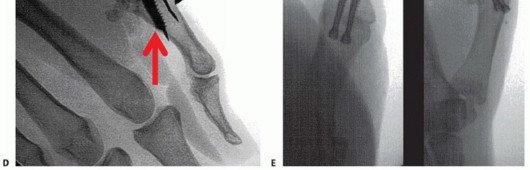

FIG 2 • X-rays showing MP joint dislocation on AP (A) and lateral (B) films. (continued)